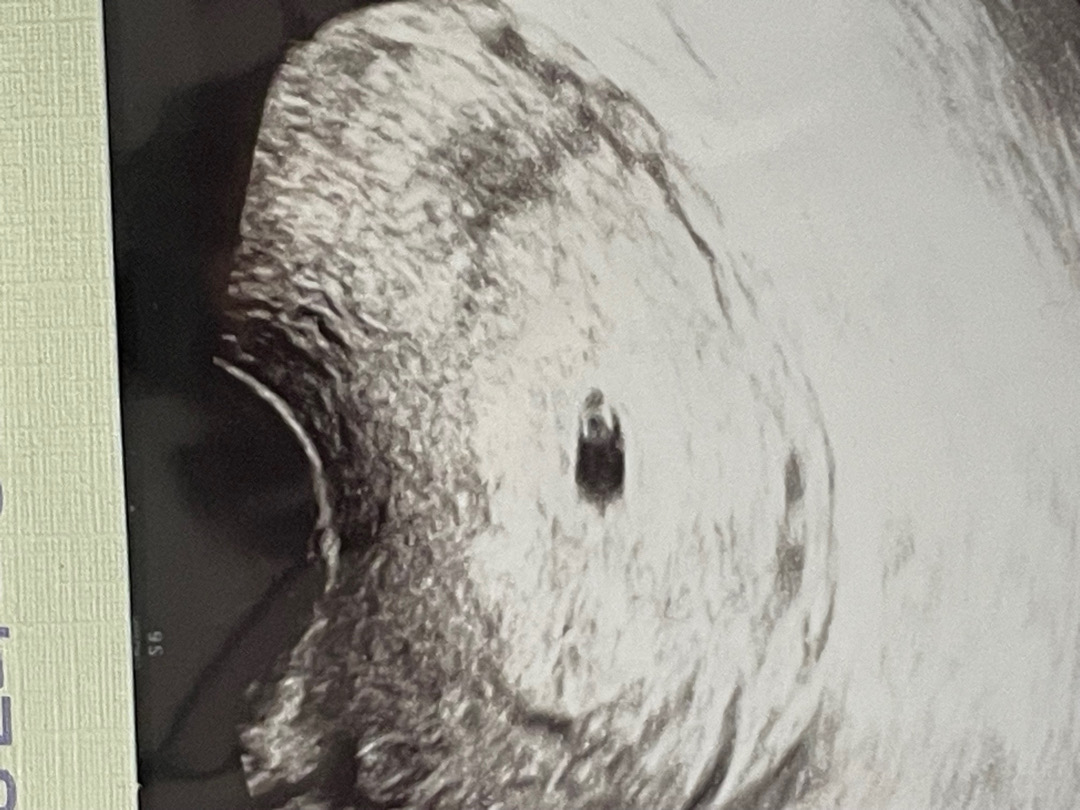

5주2일차 초음파 보고왔어요!

두줄떴을때가 3주2일이었는데 피검사로 확인받고 꾹 참다가 5주2일차 초음파 보고왔어요!! 심장소리까지 들어야 안심이 될 것 같은데 2주뒤... 정말 시간 안가네요 😭